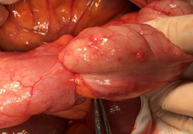

Αφαιρεθέντες πολύποδες, ενδοσκοπικά και χειρουργικά (Ευγενική παραχώρηση Dr. V. Penopoulos)

Καλόηθης πολύποδας — κορυφαίο σημείο εντύλιξης (Ευγενική παραχώρηση Dr. V. Penopoulos)